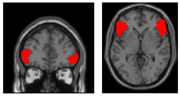

DDMを用いたfMRIデータの解析

DDMから得られたβ(DI)を手がかりに、fMRIデータを解析しました。β(DI)が小さい参加者ほど、不利な不公平が大きいときほど強く活動する領域を探したところ、背側前帯状皮質(dACC)に活動が見られました(図3A参照)。

この背側前帯状皮質が活動を抑制する脳領域を調べるため、心理生理学的相互作用解析を行いました。その結果、不利な不公平が強いとき、背側前帯状皮質と腹外側前頭前野との結合度(脳活動の相関)が負に強まることがわかりました(図3B参照)。さらに、この背側前帯状皮質と腹外側前頭前野の結合度は、不利な提案の拒否率と、不利条件における「受入れ」選択の反応時間に、それぞれ有意に相関しました(図3C、D参照)。つまり、不利な不公平が強いときに、背側前帯状皮質の活動が高まり、腹外側前頭前野の活動がより制御されると、不利な提案を受け入れやすくなるとともに、「受け入れる」までの反応時間は短くなっていました。言い換えれば、背側前帯状皮質と腹外側前頭前野のネットワークが、不利な不公平に対する受入れ/拒否を決定づけるだけでなく、「どれくらい速く受け入れるか」にも関わることが示唆されました。一方で報酬に関係する脳活動から不利な提案の拒否率と、不利条件における「受入れ」選択の反応時間の予測はできませんでした。

背側前帯状皮質 大脳半球内側面の前方部に位置する襟のような形をした領域で、競合の検出や解消、コストの計算、共感、情動など多くの重要な機能に関与している(右図の赤い部分)。 元の記事へ